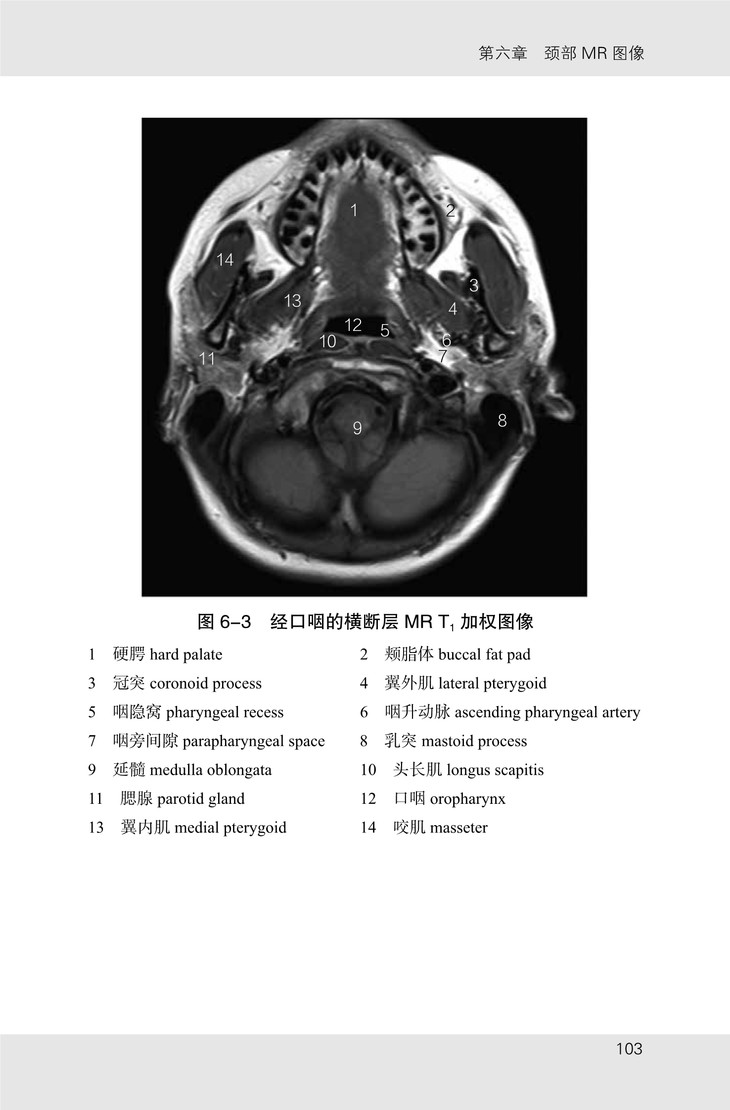

《头颈部影像解剖图谱》共包含眼眶、颞骨、鼻窦及喉部 CT 图像 107 幅,眼眶、内耳及颈部 MR 图像 70 幅。书中图像均来自山东省医学影像学研究所及济南市第三人民医院。MR 图像由 3.0T SIEMENS 磁共振扫描仪采集,序列包括 T1 加权像、T2 加权像;CT 图像由 SIEMENS 128层 CT 扫描仪采集,包括骨窗及软组织窗。

★ 内页插图 ★